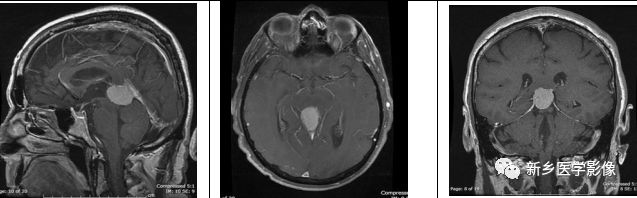

生殖细胞瘤是松果体区最常见的肿瘤。其好发于年轻男性,男女比约9:1.有时候,松果体区肿物可伴随鞍上肿物。肿瘤内无钙化,但可包绕松果体内钙化。有时,在T2WI上其可表现为稍高信号,小的囊变区可见。

矢状位及横断位T1WI+C示松果体区明显强化肿块,鞍上也可见小的强化肿块;横断位T2WI+FLAIR示松果体区高信号肿块伴周围水肿。